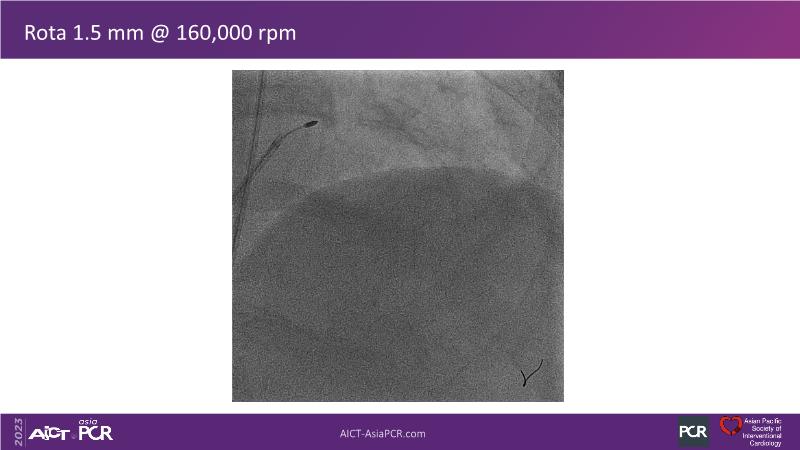

• To see advantages of RotaCUT as part of lesion preparation in left main bifurcation